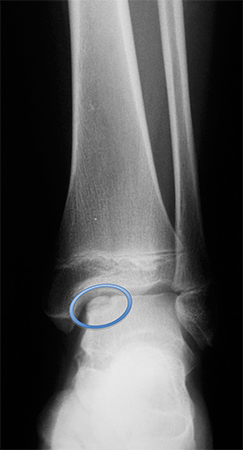

Preoperative radiograph with large osteochondritis lesion of the femoral condyle

From the collection of H. Chambers, MD